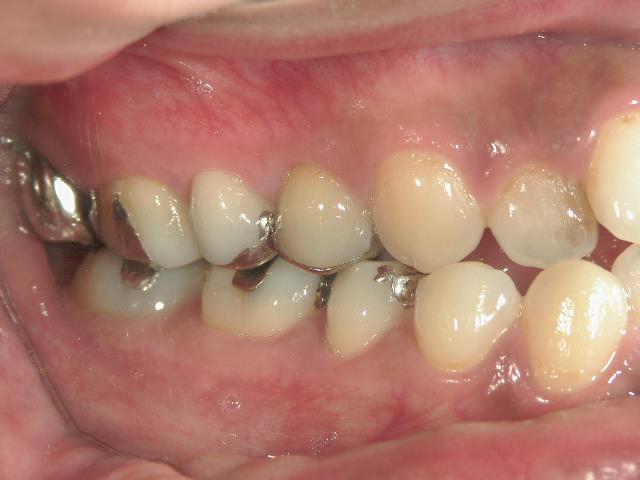

全顎ワイヤー矯正 症例(18)

30歳女性 浜松市北区在住

治療期間3年4ヶ月

主訴:前歯の歯並びが気になる。

矯正歯科 治療前 上顎を装置(QH)で拡大後ワイヤー矯正へ移行、右下5番左下4番 計2本抜歯叢生改善